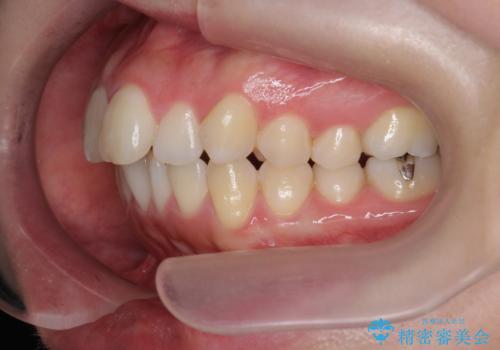

上下の歯は、上顎の歯が相対的に前に位置する咬合関係で押し出されるように前歯に角度がついている状態です。

咬合関係の改善、前歯の角度、がたつきを改善するため、マイクロインプラントを用いて上顎の奥歯を後方へ移動させていきます。

矯正治療後、前歯のがたつき、咬合関係が改善され満足いただくことができました。